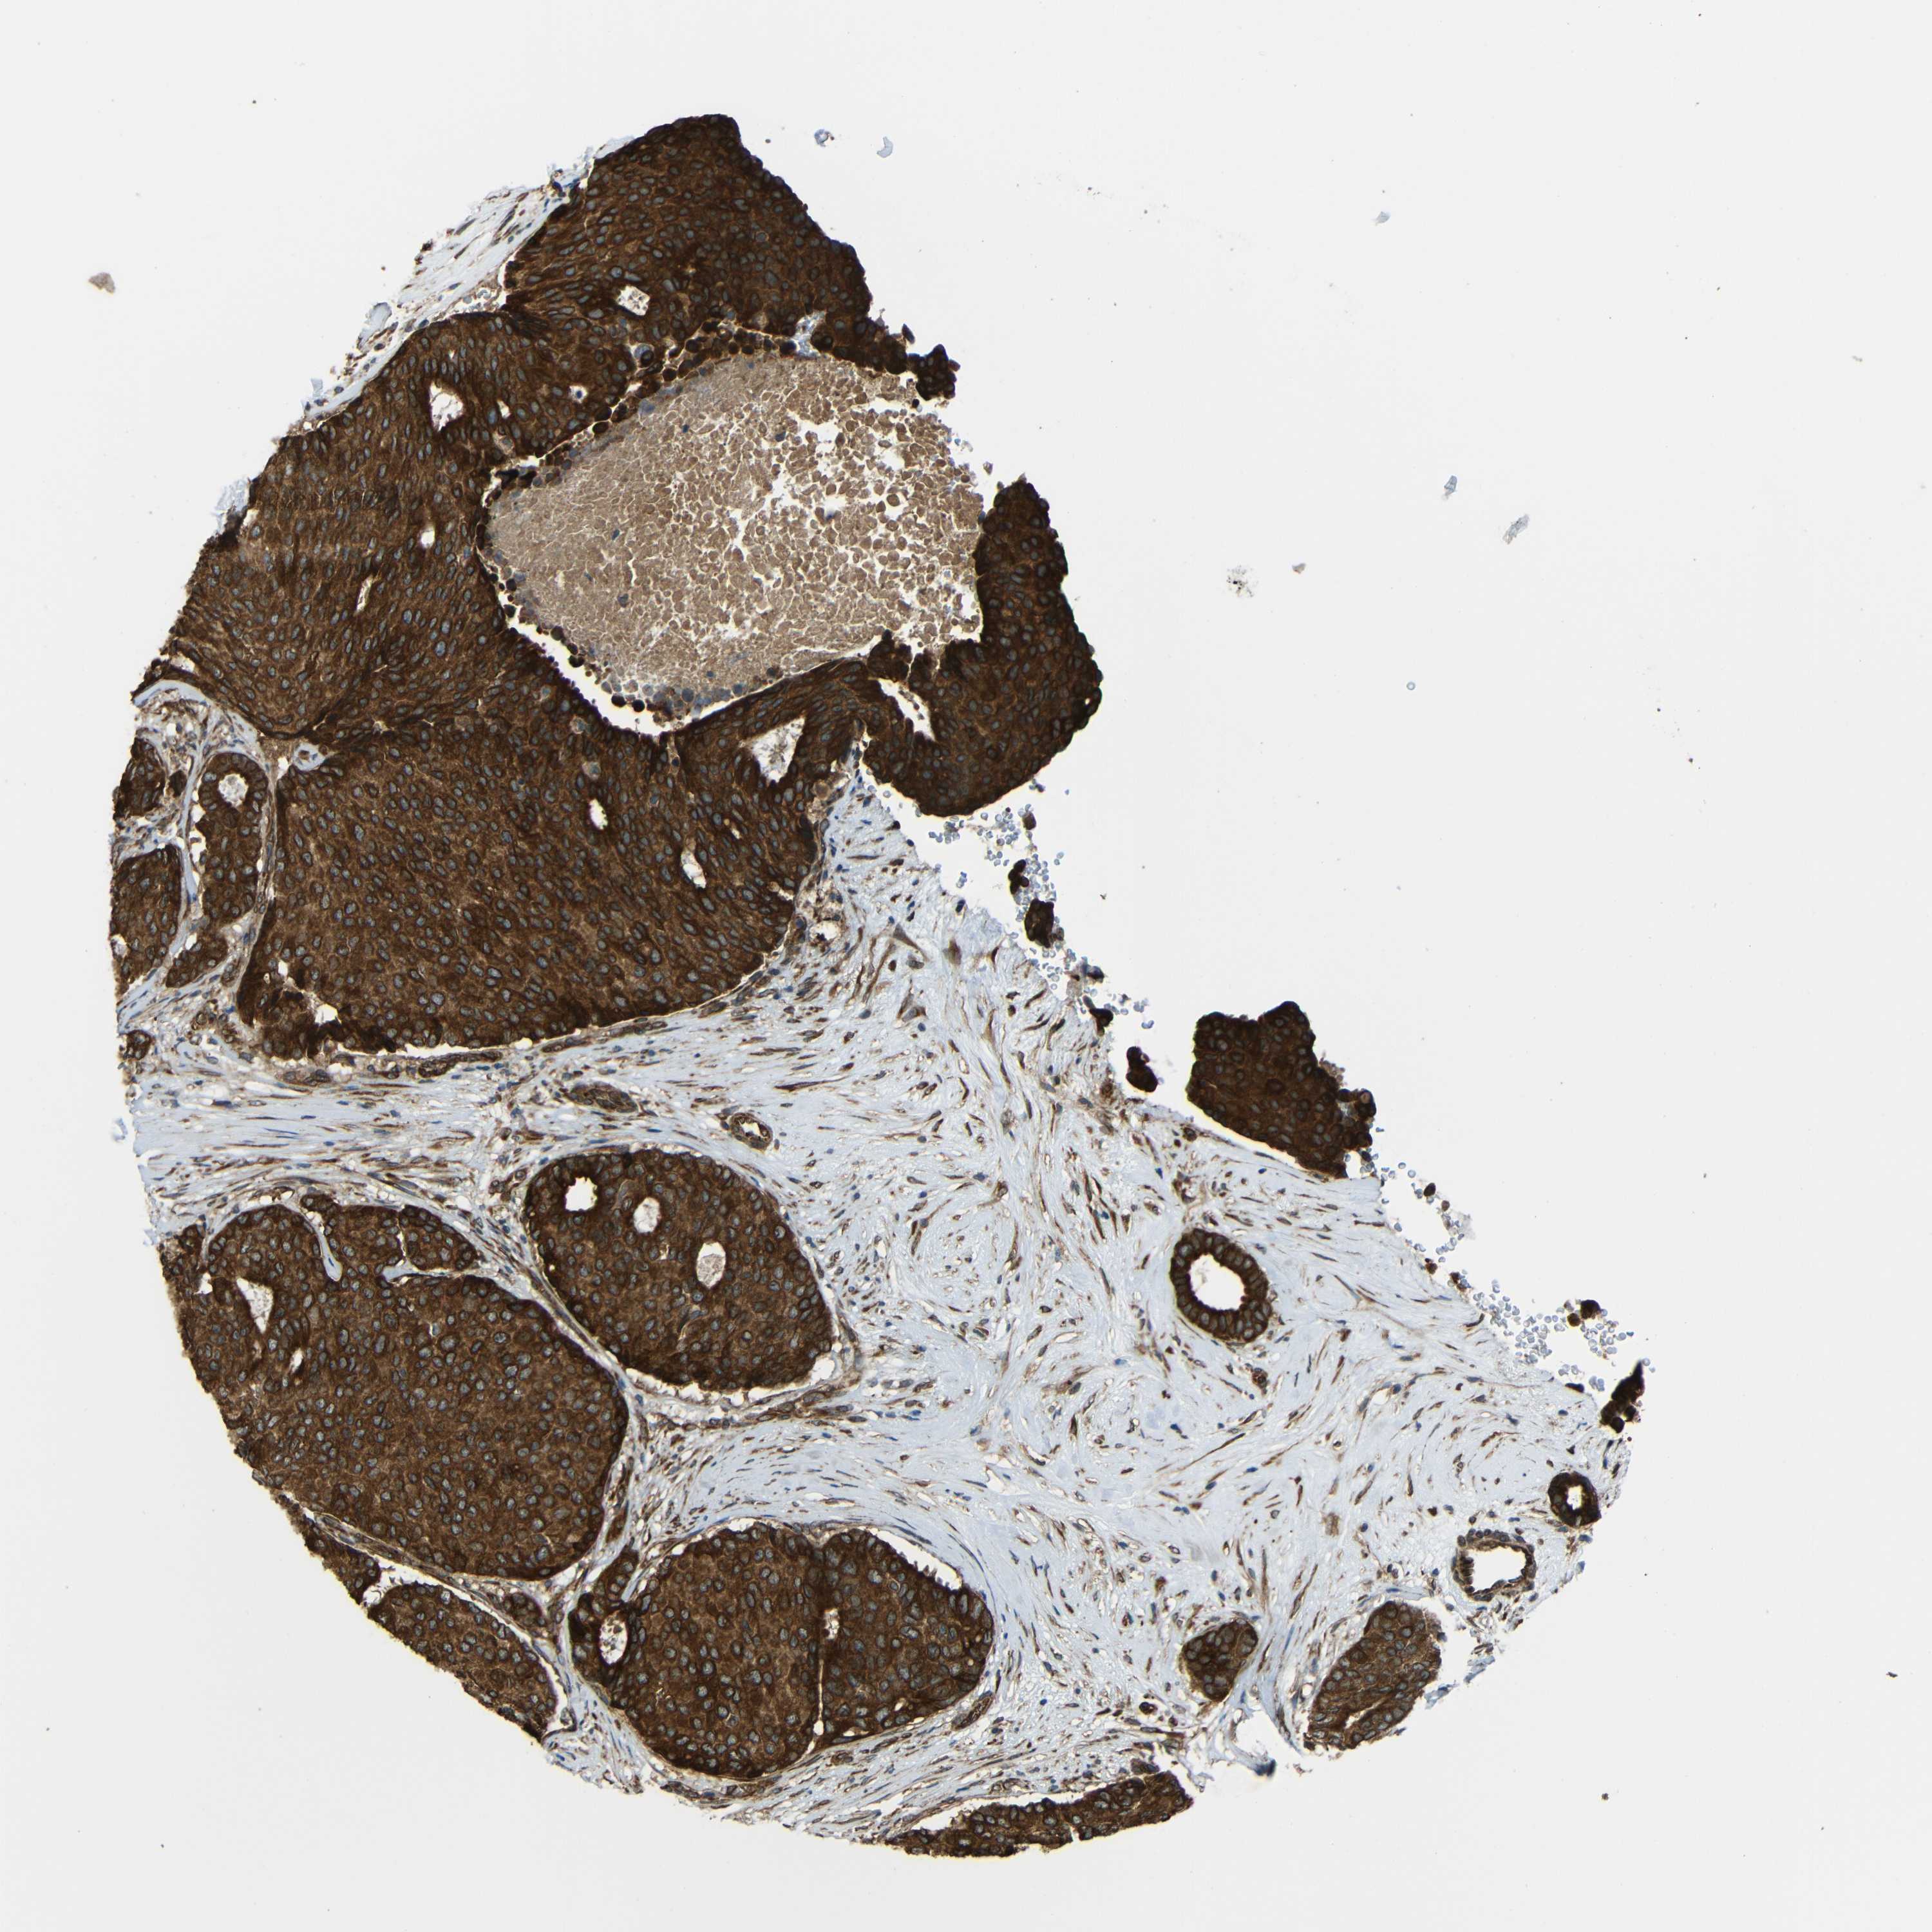

CANCER BREAST CANCER Show tissue menu

BRCA TCGA BRCA VALIDATION PROTEIN EXPRESSION